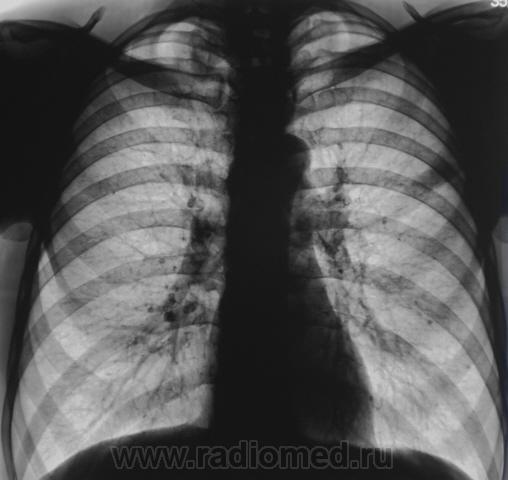

Очередной контроль после флюорографии.

без архива сложно, но похоже старые дела...

Архива нет. Человек приезжий, на ПМЖ.

Похоже, "дела давно минувших дней".